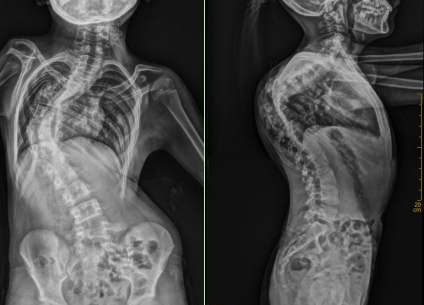

广医三院脊柱外科副主任医师秦础强帮小雨仔细检查后,发现她病情远比想象中复杂:脊柱侧凸同时合并严重后凸畸形,角度达到70度,属于典型的先天性脊柱侧后凸畸形。

考虑到小雨才11岁,脊柱侧凸的同时还存在严重的后凸畸形,甚至矫正后凸畸形比矫正侧凸畸形还要重要,经全科多次讨论后,广医三院脊柱外科吴增晖主任团队为她制定了分期手术方案——一期先通过侧路手术提前矫正部分侧凸和后凸,二期再施行后路截骨矫形手术。两期手术都顺利完成,术后第4天小雨就能下地活动了,从外观上看其脊柱畸形大幅矫正,术后影像学显示其侧凸Cobb角度减少了近40°,后凸角度也矫正到接近正常,她终于可以平躺着睡觉了。

小雨术前术后侧面对比,脊柱后凸畸形明显改善